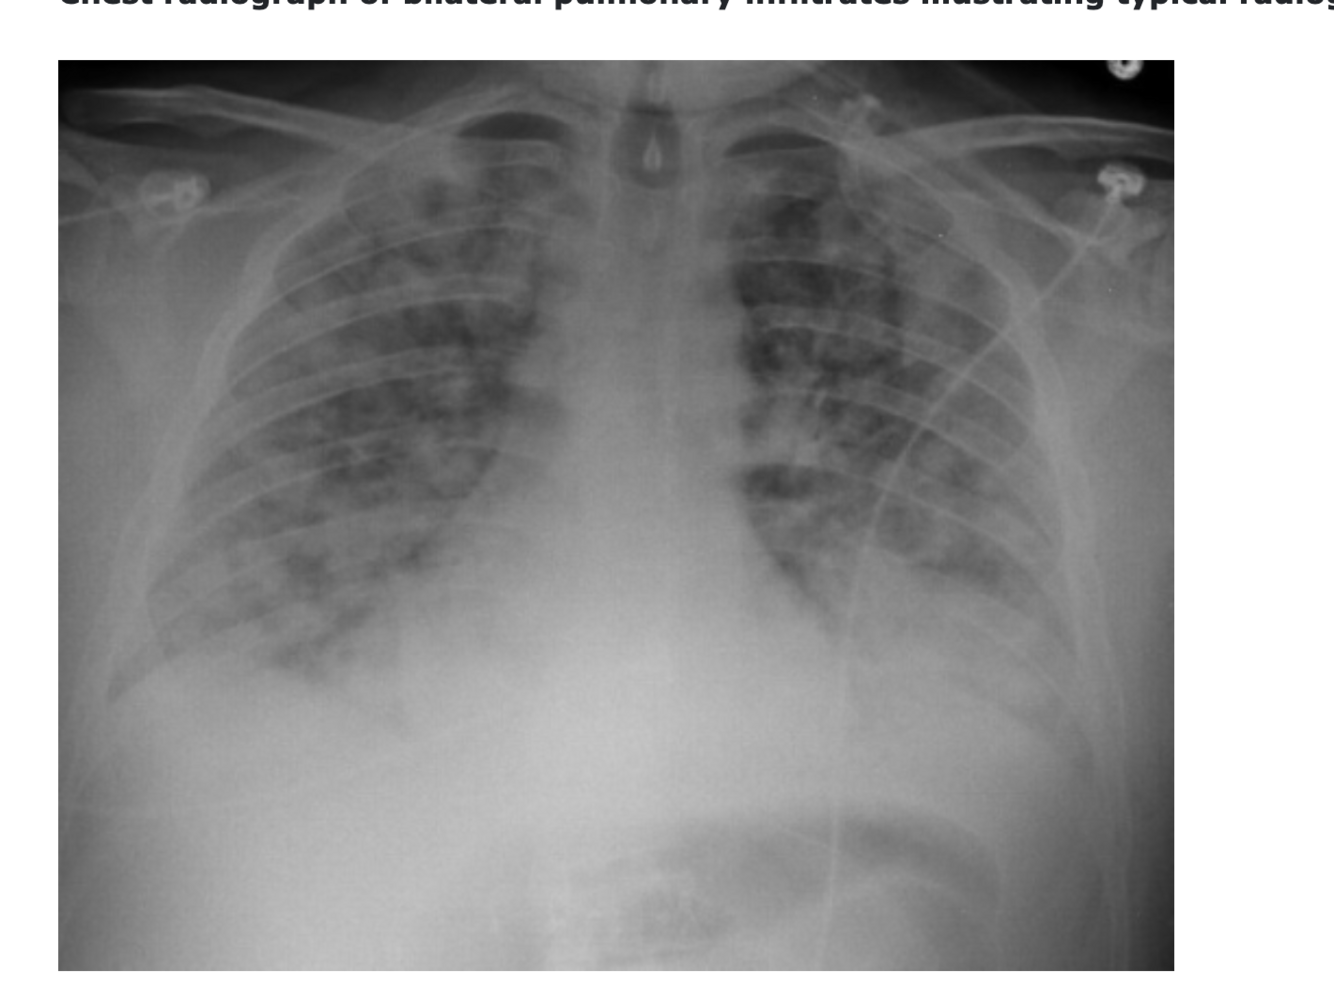

Signs/symptoms: Absence of breath fog, suprasternal and supraclavicular retractions, paradoxical chest and abdomen movements (abdominal breathing), loss of ETCO2/volumes, hypoxia, pink/frothy sputum, bilateral fluffy pulmonary infiltrates on CXR